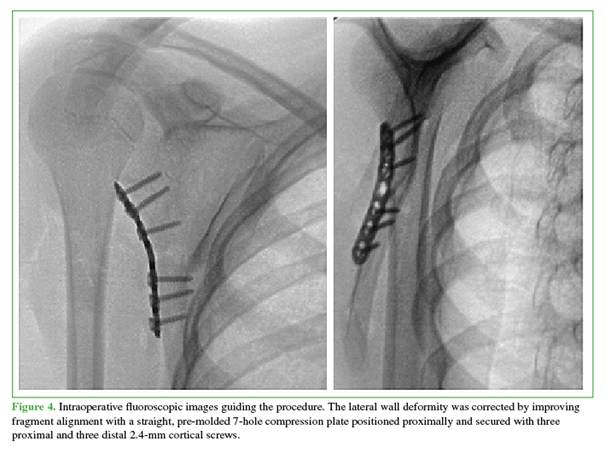

The fragments were mobilized by releasing the abundant bone callus with signs of consolidation, in order to improve fragment mobility at the fracture site and restore the length of the scapular lateral border. Reduction was achieved using reduction forceps, with provisional fixation using Kirschner wires to align the superior and inferior fragments. Together, these steps facilitated correction of the lateral wall angle, which was definitively fixed using a pre-contoured plate proximally and cortical screws along the lateral border (Figure 4).

Alignment, reduction, and implant positioning were confirmed using intraoperative fluoroscopy. Adequate screw angulation was achieved, with no intra-articular placement. The wound was closed in layers, and shoulder mobility was assessed immediately. Both passive and assisted active ranges of motion showed marked improvement. The patient continued to use an arm sling until postoperative follow-up.